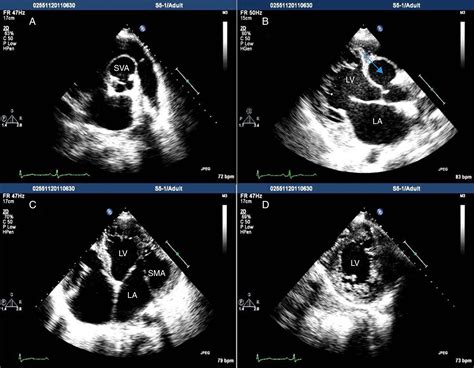

Modern medical imaging has made it significantly easier to identify and characterize an SVA. Cardiologists utilize several non-invasive and minimally invasive techniques to view the structure of the aorta and the integrity of the sinus walls:

Transthoracic Echocardiogram (TTE) The primary screening tool to visualize the aortic root and assess wall motion.

Transesophageal Echocardiogram (TEE) Provides highly detailed images of the sinuses, often used if the TTE is inconclusive.

• sinus of valsalva aneurysm echo